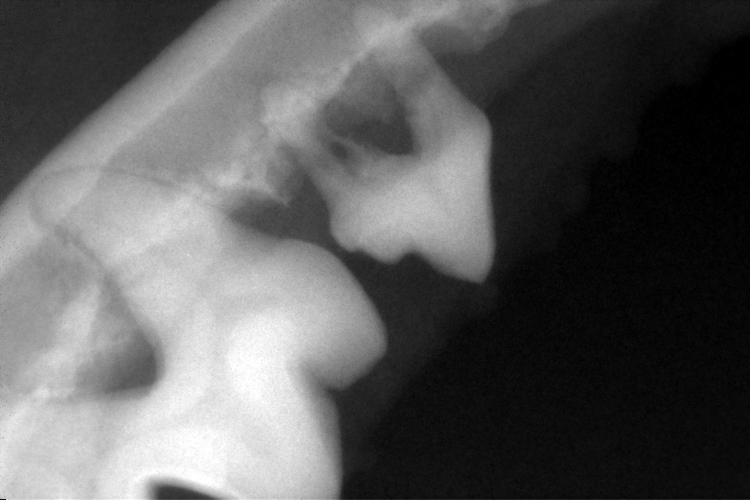

歯科レントゲン

右上顎第4前臼歯と右下顎第4前臼歯です。

黄色斜線部分の歯槽骨が溶け、黒く抜けているのが確認できます。